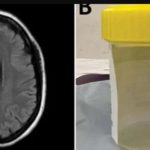

Live worm found in woman’s brain during surgery

In a world-first, scientists say an 8cm (3in) worm has been found alive in the brain of an Australian woman.

The “string-like structure” was pulled...